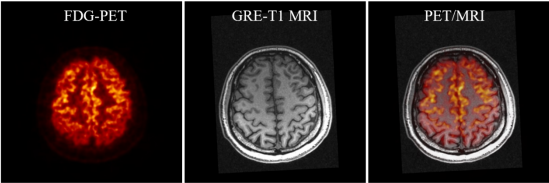

SIAT bPET和联影uMR790 3T磁共振成像系统上同时取得的人脑PET/MRI图像